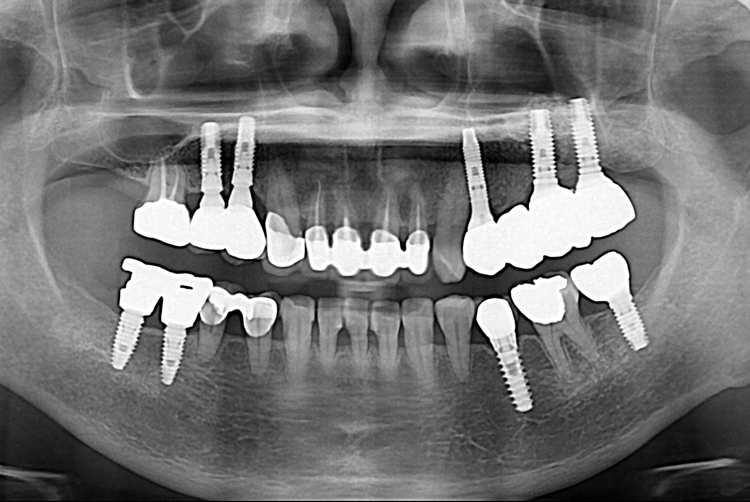

[임플란트] 어금니 임플란트

치료전 : 2018-12-12

세종치과는 많은 환자와 다양한 케이스를 바탕으로

항상 편안한 임플란트 수술을 제공하고자 노력하고,

오래동안 튼튼히 쓸 수 있는 임플란트 수술을 가장 큰 목표로 삼고 있습니다.